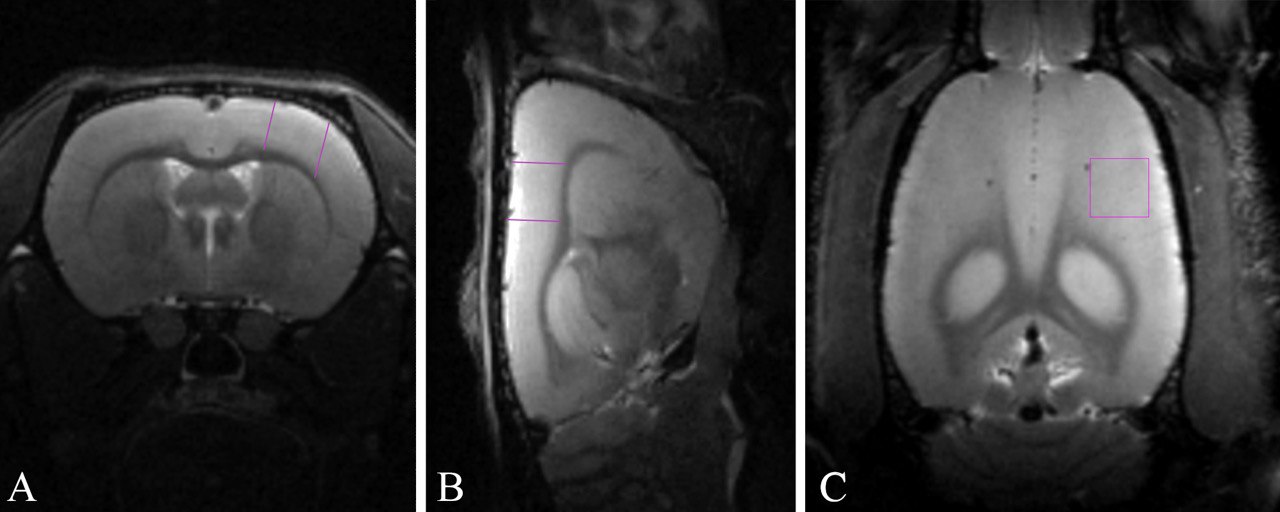

Специалисты предупреждают: в пилотируемых дальних космических миссиях, а именно - за пределами магнитного поля Земли - 70 000 километров от поверхности и дальше, экипаж подвергается значительному радиационному облучению. Ранее полученные данные МРТ мозга космонавтов, побывавших на Международной космической станции, показали, что в космосе уменьшаются в объеме практически все структуры мозга, кроме сенсомоторной коры - области, ответственной за восприятие и контроль движений тела. Такое снижение объема не влечет за собой функциональных нарушений нервной системы - ухудшения психоэмоционального статуса и когнитивных способностей. Оно ни на что не влияет, а происходит, вероятно, из-за перераспределения жидкостей в организме (физиологической адаптации). Это когда, как говорят в народе, кровь приливает к голове. Причины же, по которым условия космоса не приводят к уменьшению объема сенсомоторной коры, до сих пор не были известны.

Чтобы воссоздать эффект радиационного воздействия, с которым столкнутся космонавты в ходе реализации дальних космических миссий, исследователи в течение 24 часов облучали крыс экспериментальной группы γ-квантами (поглощенная доза 400 мГр была набрана за 24 часа непрерывного облучения). Это повысило чувствительность нервной ткани к излучению. Затем головы животных облучили потоком высокоэнергетических ядер углерода-12 (в этом случае поглощенная доза достигла 140 мГр). Суммарная эквивалентная доза оказалась примерно в три раза больше, чем та, которую получают космонавты за год пребывания на МКС. В течение семи месяцев ученые наблюдали за животными: дважды провели поведенческий анализ и сделали МРТ - через неделю и семь месяцев после облучения.

Второй паре групп крыс (контрольной и экспериментальной) авторы провели иммунофлуоресцентный анализ для оценки концентрации нейротрофинов в сенсомоторной коре. Оказалось, что при действии ионизирующего излучения количество этих белков увеличивается: нейротрофина-3 на 40% и нейротрофина-4 на 68% по сравнению с показателем у необлученных крыс. Это может быть одним из факторов, благодаря которым ионизирующее излучение препятствует истончению сенсомоторной коры. Однако причиной изменений может быть и вызванное излучением увеличение двигательной активности крыс.